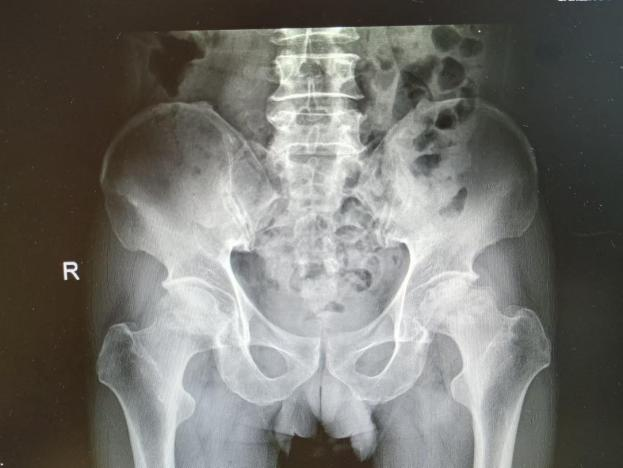

2025年11月1日,由遵义市医学会手外科分会主办、遵义市第二城市医疗集团(贵州航天医院)承办的遵义市医学会手外科分会学术交流会暨贵州省继续医学教育项目《急诊手外伤治疗临床研究新进展专题研讨班》在贵州航天医院成功举办,汇聚了遵义市手外科领域专家及基层医疗骨干,通过专题研讨与临床经验分享,共探急诊手外伤诊疗新进展。 会议特邀遵义市医学会手外科分会主任委员金文虎教授,遵义市医学会手外科分会副主任委员张子阳教授,遵义市医学会手外科分会常务委员杨绍浦教授,贵州航天医院陈明勇教授、赵兴东教授等遵义市手外伤专家进行交流分享;贵州航天医院党委委员、副院长彭亮参加会议并致辞,贵州航天医院骨科医务人员,遵义市第二城市医疗集团成员单位及红花岗区、绥阳县、桐梓县等区县医疗机构手外伤骨干参与。 贵州航天医院党委委员、副院长彭亮致辞 学术交流 本次学术交流以“急诊手外伤治疗临床研究新进展”为主题,通过理论授课与临床案例结合,共同探讨急诊手外伤临床诊疗全链条诊疗策略、关键技术、临床研究新进展,促进规范化诊疗技术向基层下沉,助力提升区域手外伤应急处置与修复能力。 贵州航天医院赵兴东教授分享《急诊手外伤的诊断与治疗原则》 贵州航天医院陈明勇教授分享《开放性骨折的治疗原则》 贵州航天医院张军教授分享《甲沟炎Winograd手术的临床应用》 贵州航天医院赵兴东教授分享《手部常见的皮肤缺损及治疗原则》 贵州航天医院张艳金教授分享《开放性骨折的清创术》 贵州航天医院冷家雄教授分享《下肢创面修复的常用皮瓣之股前外侧皮瓣》 贵州航天医院邬夏荣教授分享《踝关节慢性不稳的诊治》 贵州航天医院卢懿明教授分享《掌骨骨折》 贵州航天医院张艳金教授分享《手部肌腱的解剖与修复方法》 本次研讨班为遵义市手外科领域医务人员提供了深度交流契机,强化了医疗机构间的协作网络,进一步推动学科创新与临床实践融合,为健康遵义建设注入新动能。 贵州航天医院骨科专家简介 陈明勇 骨一科主任,副主任医师 临床擅长:从事创伤骨科工作约20年,对骨缺损、骨不连、骨肿瘤、肢体畸形等的肢体矫形重建及功能重建,慢性化脓性骨髓炎的根治治疗、糖尿病足的保肢治疗、快速康复理念(ERAS)下的老年骨折的诊治,四肢复杂骨折的诊治,四肢骨折等微创手术治疗具有丰富的临床经验。 2004年毕业于遵义医学院临床专业,曾在中国人民解放军总医院、广西医科大学第一附属医院、上海第六人民医院骨科进修。中国中西医结合学会骨伤科专业委员会横向骨搬移治疗糖尿病足及微血管网再生学组首届委员,遵义市医学会创伤分会常务委员。 瞿 晖 骨科党支部书记,骨二科主任,副主任医师 临床擅长:对骨科的常见病、关节外科、脊柱外科及运动医学疾病的诊治具有丰富的临床经验,熟练掌握骨科手术操作技术。 毕业于遵义医学院临床医学系,2005年前往广州中山大学第一附院骨显微医学部进修学习,2011年前往成都华西医院进修学习,并多次在省内外学习骨科相关知识,是中华医学会骨科分会会员。 赵小锋 中共党员,骨二科副主任,副主任医师 临床擅长:从事骨科临床工作11年,对骨科常见病、多发病诊疗有较为丰富的临床经验,擅长脊柱相关疾病诊断及治疗,尤其是颈、腰、腿疼痛疾病诊断及治疗,擅长胸腰椎骨折微创经皮穿刺内固定术、经皮穿刺椎体成形术、经皮穿刺脊柱内镜下腰椎间盘摘除术、单纯开创腰椎间盘摘除术、腰椎滑脱复位椎间植骨椎融合内固定术、腰椎管狭窄减压融合内固定术及人工髋、膝关节置换术等。 2012年毕业于遵义医学院外科学专业硕士研究生,2019年参加“遵义市115医学人才精英计划”于上海交通大学第一附属医院培训学习,2023年于北京大学第三人民医院脊柱外科进修学习,曾获得遵义市优秀医师荣誉称号。 遵义市手外科第一届委员,遵义市医学会创伤分会第一届委员,遵义市医学会创伤分会第二届委员,贵州省康复医学会第三届脊柱脊髓专业会委员,遵义市医学会烧伤与整形外科学分会委员,发表论文5篇,其中国家级核心期刊1篇,SCI论文1篇,主持市级课题1项并结题,参与市级课题2项。 赵兴东 骨科主任医师 临床擅长:擅长骨科的常见病及各种创伤、四肢骨折创伤修复、骨感染、手足疾病的诊治和手足体表畸形的矫形整复,熟练掌握骨科四肢骨病及创伤的手术操作技术,尤其在四肢关节复杂性损伤、手足外伤、组织缺损创面、难治创面的皮瓣修复方面及平足、高弓足矫形方面及四肢慢性疼痛诊治、康复方面具有丰富的临床经验。 硕士研究生,毕业于遵义医学院临床外科系,2015年前往山东省立医院手足外科进修学习;遵义市医学分会创伤分会第一、二届委员,遵义市手外科医学会第二委届员会常务委员;在省级及省级以上期刊发表文章9篇,参编著作2部,参与主持并完成市级课题1项,参与市级课题2项、省级课题1项。 张艳金 中共党员,骨科副主任医师 临床擅长:从事骨外科工作16年,对复合伤、多发伤的救治、四肢骨干骨折、关节周围骨折、骨肿瘤、骨髓炎等诊治具有丰富的临床经验。 中共党员,硕士研究生,2006年本科毕业于山西医科大学第二临床医学院,2011年研究生毕业于北京军区总医院;在“老年COPD患者合并髋部骨折的诊治”国际合作课题组研究两年,在老年髋部骨折的诊治方面具有丰富的经验,并发表论文6篇;主持遵义市级课题1项,承担遵义医科大学的临床教学工作,获得遵义医科大学优秀带教老师荣誉。编撰有《骨科疾病诊疗精粹》一书,开展2项新技术,编撰地方规范《务川自治县创伤骨科常见疾病诊疗规范》一书。 张俊凯 骨科副主任医师 临床擅长:从事骨科临床工作28年,对创伤骨折、骨感染、骨缺损、骨不连等外科诊治,四肢骨折的微创手术治疗,四肢复杂骨折(如关节内粉碎性骨折、多发骨折等)的损伤控制及手术治疗等具有丰富的临床经验。 1995年毕业于遵义医学院临床专业,2009年前往复旦大学附属医院骨科进修1年。 卢懿明 中共党员,骨科副主任医师 临床擅长:从事骨科工作18年,对创伤骨折、四肢骨折的微创手术治疗、四肢复杂骨折(如关节内粉碎性骨折、多发骨折等)的损伤控制及手术治疗,尤其是髋部骨折的PFNA等微创技术,踝关节骨折、膝关节周围骨折的Mipo微创技术等具有丰富的临床经验,开展了4项新技术,发明6项新型专利技术。 2005年毕业于遵义医学院临床专业,2017年,前往南方医科大学第三附属医院骨科进修半年,回院后运用Mipo技术对骨干骨折及干骺端骨折的治疗技术,同时积极开展骨盆骨折、髋臼骨折腹直肌外侧切口的应用;发表了多篇专业论文,经常参与省内外学术交流会授课,获得医院荣誉称号多个。 邬夏荣 骨科副主任医师 临床擅长:从事骨科工作16年,对四肢复杂骨折、骨肿瘤的诊治,尤其是足踝创伤、慢性踝关节损伤、平足症等诊疗具有丰富的临床经验。 2006年毕业于遵义医科大学临床医学专业,曾在陆军军医大学西南医院进修学习,发表多篇骨科学术论文。 余德怀 中共党员,骨科副主任医师 临床擅长:从事骨科工作10余年,对运动医学、骨关节、脊柱外科常见病、多发病的诊治具有丰富的临床经验。 硕士研究生,2011年毕业于遵义医学院临床医学专业,曾前往遵义医科大学附属医院运动医学专业进修学习;是贵州省医学会运动医学分会青年委员,西部关节镜联盟委员;发表多篇骨科学术论文。 冯 乾 骨科副主任医师 临床擅长:从事骨科工作近20年,熟练掌握骨科多发病及常见病的诊治,尤其对脊柱退变性疾病的诊断及治疗具有丰富的临床经验,主要研究脊柱微创相关治疗方式,能熟练开展椎间孔镜及UBE。 曾前往北京大学第三医院进修学习疼痛及椎间孔镜、首都医科大学友谊医院专业进修脊柱内镜;是贵州省康复医学会第三届脊柱脊髓专业委员会委员;发明专利3项、发表脊柱外科专业论文多篇。 贵州航天医院骨科简介 基本情况 贵州航天医院(原3417医院)骨科组建于1968年,前身是以创伤和断肢(断指)再植闻名于世的上海市第六人民医院骨科,中国断肢(断指)再植的奠基者、中科院院士陈仲伟等专家莅临科室指导医疗和教学,并在70年代开展了贵州省首例断肢(断指)再植手术。组建50余年来,诊治患者已逾百万,挽救了无数的伤病员,成为了保障遵义地区人民群众健康的重要支撑。 经过几代人的不懈努力,今天的骨科,已由创伤骨科发展至骨病、骨肿瘤、骨结核等领域,现有脊柱外科、关节外科、四肢创伤、手足外科四个亚专科,成为了集医疗、教学、科研于一体的综合学科,是贵州省临床重点专科、遵义市临床重点专科、遵义市骨科临床医学中心、遵义市基层骨科专科联盟理事长单位。 科室目前开放床位110张,共有医护人员50余人,副高级以上专家18人,硕士研究生15人。拥有一流骨科医疗设备多台,每年不定期选派优秀技术骨干到全国各大知名医学院校进修、学习、参观、交流,并邀请国内、国外知名专家教授来院进行交流、指导,通过不断引进国内外先进的诊疗技术,科室医疗技术水平稳步提升,为广大人民群众提供了优质的医疗服务。 专科特色 骨一科 (一)骨缺损、骨不连的肢体与功能重建 胫骨横向骨搬移技术治疗糖尿病足: (二)慢性骨髓炎的根治治疗 (三)肢体缺血性疾病如糖尿病足、脉管炎的保肢治疗 (四)皮瓣修复 (五)复杂创伤的治疗 (六)老年髋部骨折及小儿骨折快速手术 老年髋部骨折: 骨二科 (一)胸腰椎骨折微创经皮椎弓根螺钉固定术 (二)老年性骨质疏松性患者腰椎滑脱脊柱内固定术(骨水泥螺钉) (三)V形双通道脊柱内镜技术(VBE)腰椎融合术治疗腰椎退行性疾病 (四)老年性骨质疏松性骨折(PVP/PKP)术 (五)人工髋关节置换术 (六)双侧股骨头坏死人工全髋关节置换 (七)右侧全髋置换术后假体周围骨折翻修 (八)人工膝关节置换术 (九)人工膝关节假体松动翻修 (十)关节镜技术 传统手术切口 关节镜技术切口 诊疗范围 骨一科 1.四肢创伤、矫形。 2.手、足踝外科。 骨二科 End